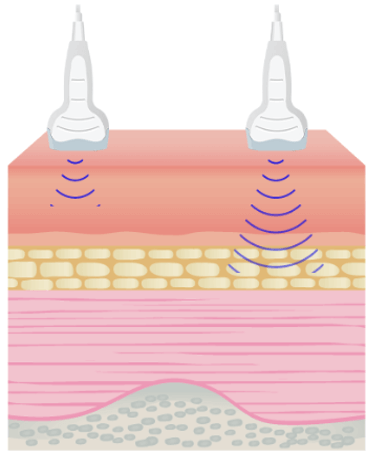

The amplitude and intensity of ultrasound waves decrease as they travel through tissues. Theoretically, the attenuation coefficient (μ) in soft tissues, is almost proportional to the ultrasound frequency and depth, with a range between 0.5 and 1 dB / (MHz.cm).

The attenuation is one of the parameters that limit the maximum frequency. It is important to note that lowering the frequency improves the depth of exploration because the ultrasound attenuation primarily increases with frequency. The maximum depth of exploration with a center frequency of 20 MHz is approximately 6-10 mm.

The sound energy is attenuated or weakened as it passes through the tissues. In fact, as the ultrasound wave travels through a medium, parts of it are reflected, scattered, absorbed or refracted.

Absorption

- The higher the frequency, the greater the attenuation

- As the attenuation increases, the depth of exploration decreases